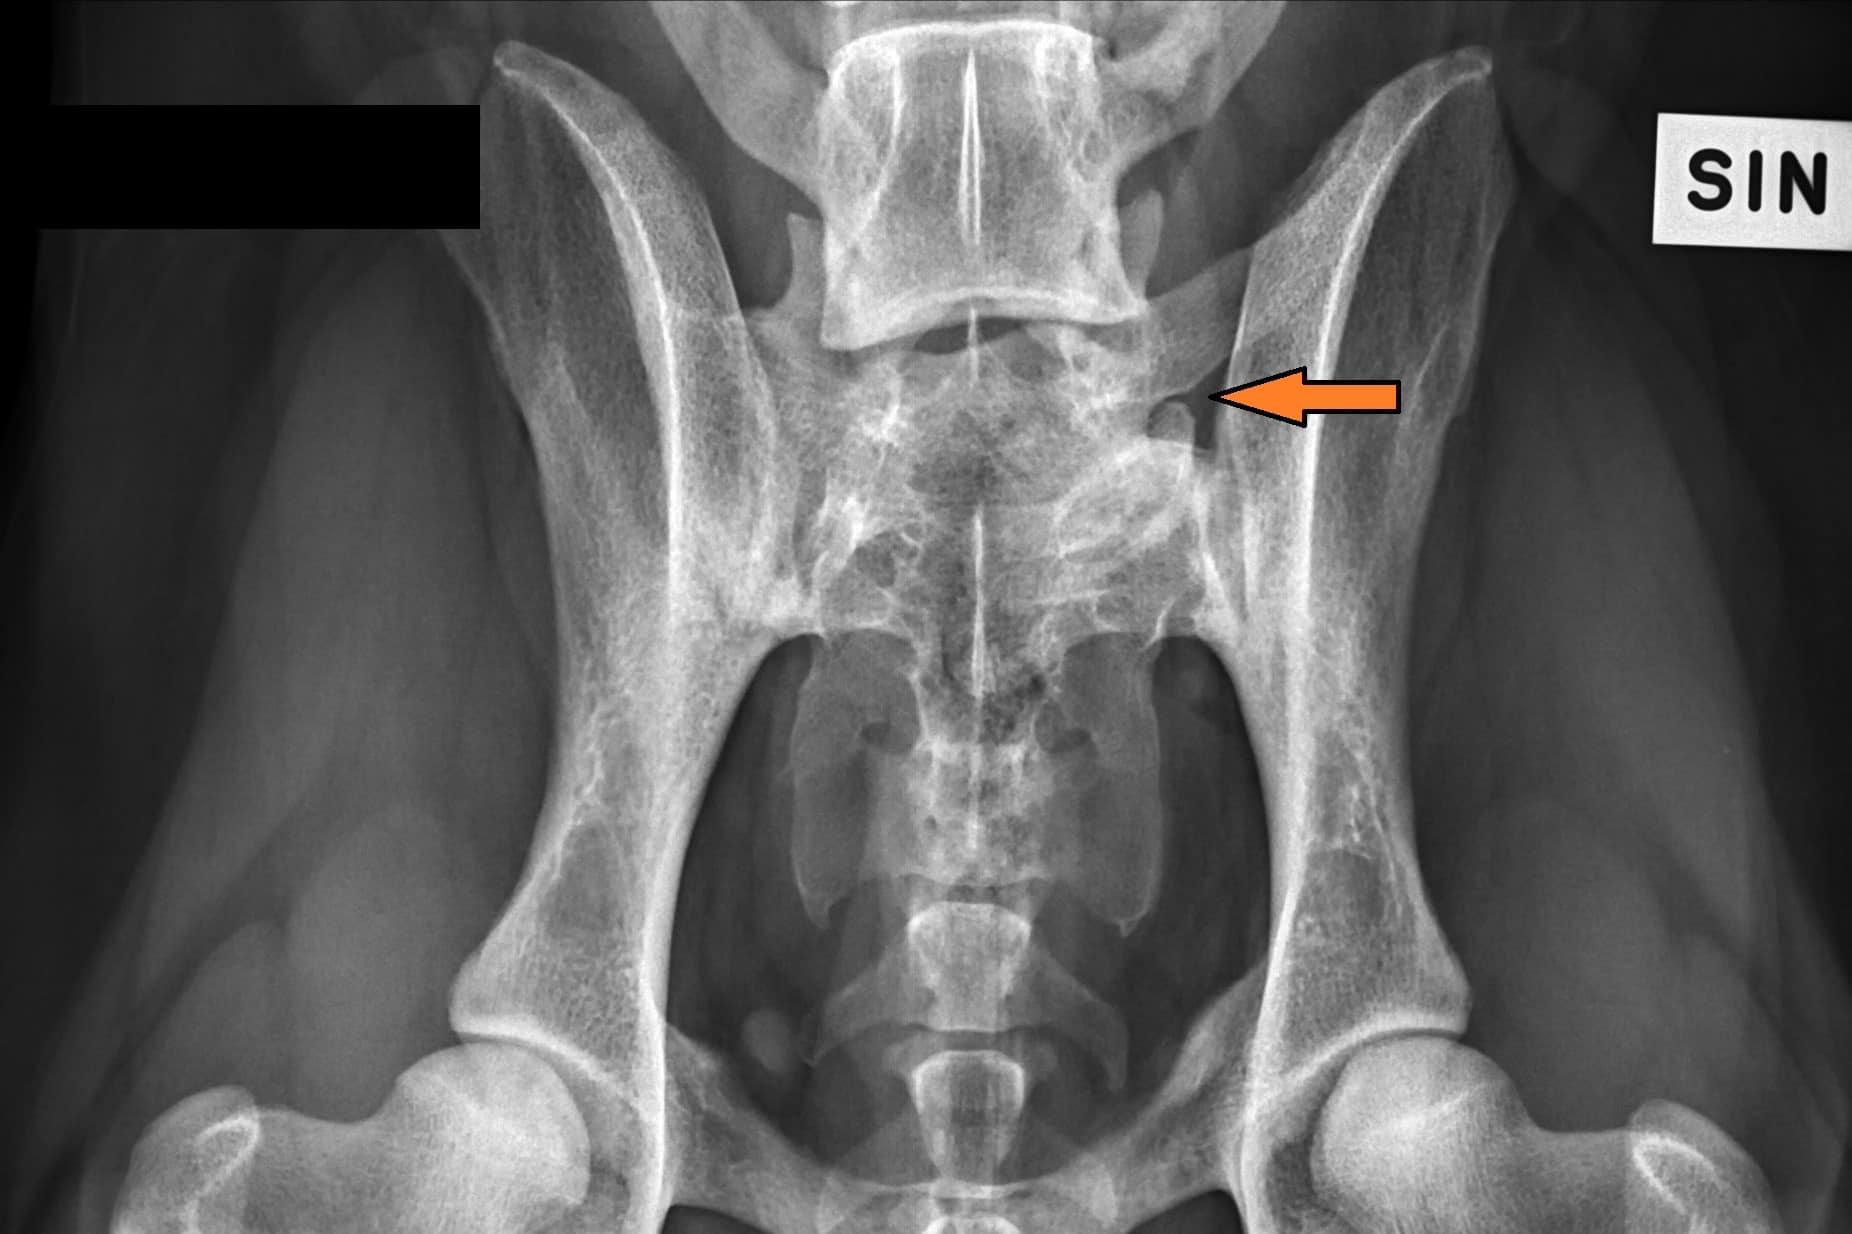

LTV2; symmetrinen

LTV3; epäsymmetrinen; oikeanpuoleisessa VD-kuvassa S1 on vasemmalla puolella ristinikaman ja oikella puolella lannenikaman kaltainen okahaarakkeen kera.

LTV3, epäsymmetrinen lanne-ristinikama näyttää olevan muita muotoja harmillisempi. Joissain tapauksissa epäsymmetriseen lanne-ristinikamaan liittyy vino lantio, joka saattaa aiheuttaa myös lonkkien epätasaista kehitystä. Tämä on varsin loogista; kun lantio on vino kohdistuu paine lonkkamaljoille epätasaisesti. Pidemmän ajan kuluessa epätasapaino voi kuluttaa toista lonkkamaljaa nopeammin ja aiheuttaa tätä kautta nivelrikkoa.

KoiraNetin mukaan 38,9% LTV3-lausunnon saaneista rhodesiankoirista on saanut lonkkien osalta lausunnon, jossa toinen lonkka on 1-2 astetta toista huonompi, esimerkiksi A/C (lokakuu 2020). Tutkimustulos LTV3 ei kerro koiran lantion asentoa.

”Asymmetrical LTV favours pelvic rotation over its long axis, resulting in inadequate femoral head coverage by the acetabulum on one side. Inadequate coverage of the femoral head favours subluxation, malformation of the hip joint, and secondary osteoarthritis. Asymmetrical hip conformation may therefore be the sequela of a LTV and mask or aggravate genetically induced canine hip dysplasia.”

(Flückiger M., Frank Steffen F. et al 2017)